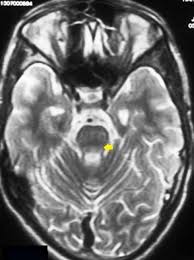

6 8 Neurologic WD is one of the main forms of the disease. In Wilson disease WD T2T2weighted T2w MRI frequently shows hypointensity in the basal ganglia that is suggestive of paramagnetic deposits. It is currently unknown whether this hypointensity is related to copper or iron deposition.

Interval changes on follow-up MR imaging were also closely correlated with clinical findings and. MRI of the brain appears to be more sensitive than CT scanning in detecting early lesions of Wilson disease. The face of the giant panda sign panda sign of the midbrain or double-panda sign is a characteristic pandas face appearance in magnetic resonance imaging MRI images of people with Wilsons disease.

The neurologist was looking for typical symptoms. Wilson disease also known as hepatolenticular degeneration is a multisystem disease due to abnormal accumulation of copper. It is characterized by early onset liver cirrhosis with CNS findings most frequently affecting the basal ganglia and midbrain.

1 In addition a second miniature panda face can be seen in the high signal abnormality in the pons figure C. To describe the spectrum of brain abnormalities in Wilson disease hepatolenticular degeneration as depicted at magnetic resonance MR imaging and computed tomography CT and to relate these findings to neurologic and hepatologic abnormalities.

To describe the spectrum of brain abnormalities in Wilson disease hepatolenticular degeneration as depicted at magnetic resonance MR imaging and computed tomography CT and to relate these findings to neurologic and hepatologic abnormalities. Positive findings believed secondary to this condition were found in 15 subjects. It is found worldwide with a prevalence of approximately 1 case in 30000 live births in most populations. Thirty-eight patients with biochemically proven Wilsons disease underwent magnetic resonanceimaging MRI of the brain as well as neurological examinations. Fifty patients with Wilson disease participated in the cross-sectional. The face of the giant panda sign panda sign of the midbrain or double-panda sign is a characteristic pandas face appearance in magnetic resonance imaging MRI images of people with Wilsons disease. 1 In addition a second miniature panda face can be seen in the high signal abnormality in the pons figure C.